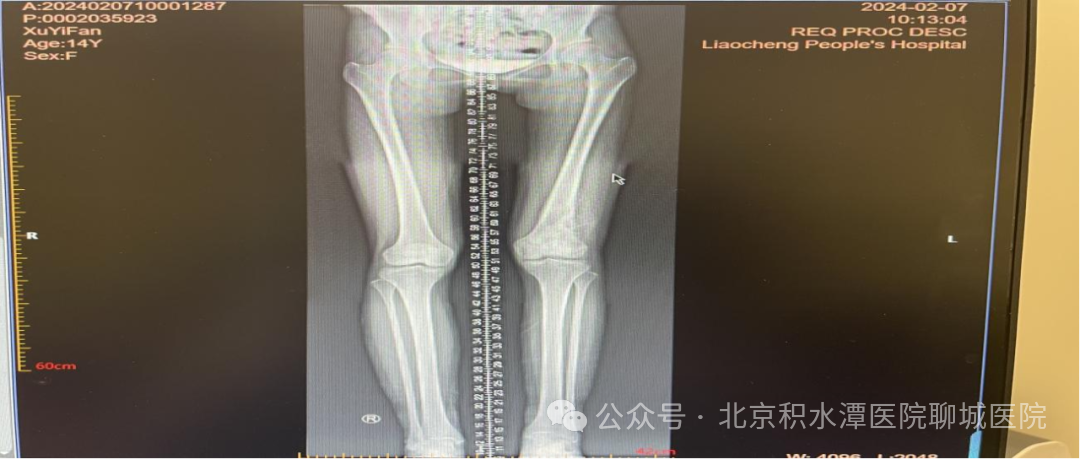

2024-02-07下肢全长拍片(DR) :左股骨远端骨肉瘤。右侧股骨、双侧膝关节、胫腓骨干未见明显异常。

2024-02-07 10:00 左侧股骨正侧位(单侧)DR :左股骨远端骨肉瘤治疗后复查(病变范围较前变化不明显),请结合临床。左胫腓骨未见异常。 疗效评价(RECIST 1.1标准):好转的SD。